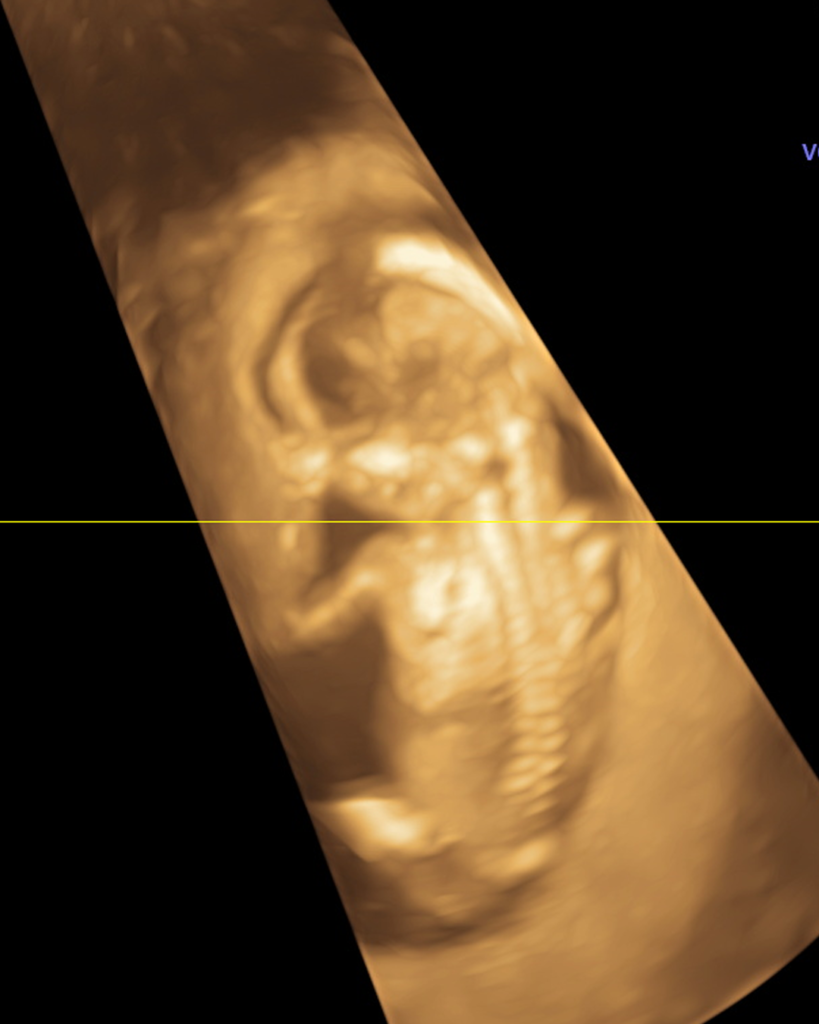

Nossas imagens

Veja algumas de nossas imagens